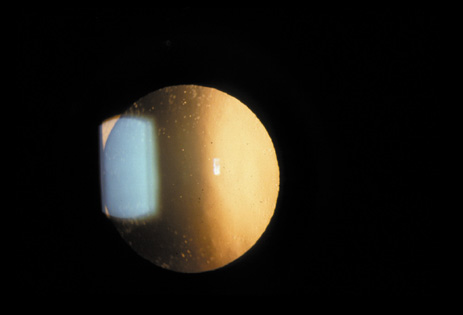

The PSC is the least prevalent subtype in most population-based studies.18 These cataracts often occur in combination with nuclear or cortical cataracts in the later stages. They are easily noticed on retroillumination because they are usually located centrally, and may interfere with funduscopy (Fig. 12). In early stages, patients usually complain of subjective symptoms such as glare disability32 and difficulty focusing on near objects. This is because when the pupil constricts during accommodation, the light entering the eye becomes concentrated centrally, where the PSC is also located. This causes light scattering and interferes with the ability of the eye to focus an image on the macula. In addition, these opacities lie at or near the nodal point of the eye, further interfering with focusing of the image on the macula.

Fig. 12. PSC. Note the central location, which gives rise to severe glare disability.

One can examine this type of cataract with direct illumination, using the narrow and broad beams of the slit-lamp to show the characteristic granular inner surface immediately in front of the posterior capsule (Fig. 13). The problem with this technique, however, is that patients may not tolerate any prolonged direct illumination because of the glare. Retroillumination is therefore more useful for revealing the outline of the opacity, since it is usually seen as an “island” in the center of the posterior capsule, which is further highlighted by the shadow cast by the opacities.33 However, in the early stages of this type of cataract, the dust-like particles that might be noticeable in the central posterior subcapsular area with direct illumination disappear or are difficult to see with retroillumination (Fig. 14). Eventually this “dusting” becomes dense enough to cast a shadow and thus appear on retroillumination. The smooth orange background of the fundus helps to highlight the rough, irregular pseudopodia-like edges of the central opacity. In advanced stages, the PSC may become a thick, calcified plaque (Fig. 15). During surgery, excessively vigorous scraping or vacuuming of the calcified opacity can lead to rupture of the posterior capsule. Usually, small remnants that are left behind after surgery are reabsorbed and do not interfere with vision; otherwise, they are easily treated with a neodymium : yttrium (Nd:YAG) aluminum garnet laser. Pathologic evidence suggests that most PSCs result from the migration of bow region cells into the potential space (along with accumulated cellular debris) between the posterior capsule and the cortex.34–36

Fig. 13. Direct slit-lamp illumination of a PSC, showing an irregular granular surface in front of the posterior capsule.